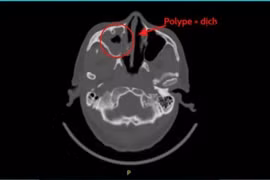

Bệnh nhân 53 tuổi nhiều tháng đau đầu không rõ nguyên nhân, chụp CT phát hiện nấm xoang bướm. Đây là bệnh hiếm gặp nhưng biến chứng rất nguy hiểm.